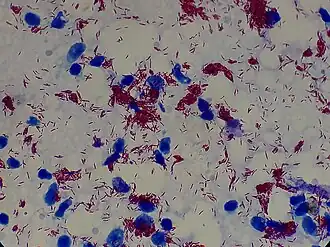

Mycobacterioum leprae and Mycobacterium lepromatosis are the mycobacteria that cause leprosy.[29] M. lepromatosis is a relatively newly identified mycobacterium isolated from a fatal case of diffuse lepromatous leprosy in 2008.[5][30] M. lepromatosis is indistinguishable clinically from M. leprae.[31] M. leprae is an aerobic, rod-shaped, acid-fast bacterium with a waxy cell envelope characteristic of the genus Mycobacterium.[32] M. leprae and M. lepromatosis are obligate intracellular pathogens and cannot grow or be cultured outside of host tissues.[5][33] However, they can be grown using research animals such as mice and armadillos.[34][35]